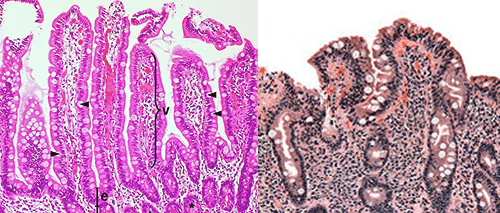

celiac disease

villi flattened, damaged, or not present

disorder of the small intestine

gluten reacts with the lining of the small intestine, leading to an attack by the immune system and damage to the microvilli and villi

-if left untreated, can lead to malabsorption, anemia, bone disease, and rarely, cancer

treatment: avoid eating food with gluten

histological features: villous atrophy, inflammatory cells